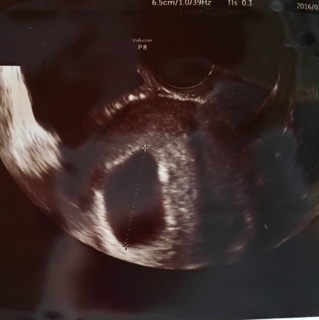

3回目…2月21日

手術前日

今日は非常勤の先生なのか、初めてあう方

もう一度、エコーで確認していく

”あれっ、ここに卵黄嚢が見えるね”と

んっ??確かになんか見える?

排卵がかなり遅れていたのかも

と、グラフを書いて説明して下さって、今日は、手術の準備はやめて、もう一度明日、担当の先生に診てもらいましょうと、その日は帰宅しました?